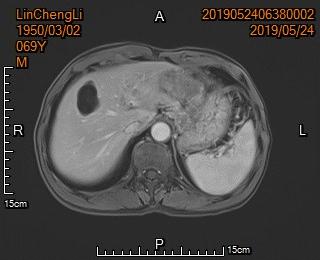

病例1

老年男性,胃癌晚期腹腔广泛转移,肿瘤侵犯导致幽门梗阻,胃部肿瘤溃烂出血。

针对患者具体病情,先予以行胃癌动脉栓塞止血,空肠营养管置入以便长期肠内营养支持、改善体质。